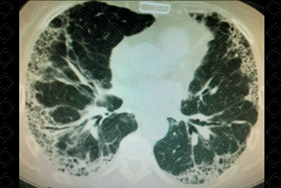

Texto alternativo para a imagem Figuras 1 e 2. Créditos: Dra. Elazir Mota - Rio de Janeiro/RJ

Descrição das figuras 1 e 2: Tomografia computadorizada do tórax, cortes axiais evidenciando opacidades reticulares, vidro fosco e cistos de faveolamento, com predileção periférica, em situação subpleural.

• Tomografia computadorizada do tórax: C aracteriza-se como padrão típico para PIU a presença de opacidades reticulares de predomínio periférico e basal, associado a faveolamento, estando presentes ou não bronquiolectasias de tração (figura 1). Outras manifestações típicas do padrão de pneumonia intersticial usual na TC consistem em linhas intralobulares e espessamento irregular de septos interlobulares, resultando em padrão reticular, distorção arquitetural pulmonar, bronquiectasia, bronquiolectasia de tração e faveolamento.